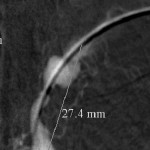

The 4 images you see above were recorded by me during primary stenting of irregular atherosclerotic stenosis of the left subclavian artery in a 54-year-old hispanic female who was referred to my interventional radiology clinic for management of the stenosis. She had presented to her primary care physician with symptoms of hindbrain ischemia upon using her left upper limb and earlier workup confirmed left subclavian arterial stenosis. The 2 top images illustrate the character and severity of her disease, the first image in the bottom row shows the process of balloon-expandable stenting of the disease, while the 2nd image in the bottom row reveals complete elimination of the stenosis and reappearance of the left vertebral and internal mammary arteires, which were invisible on the pre-intervention angiograms reflecting the severity of the stenosis.